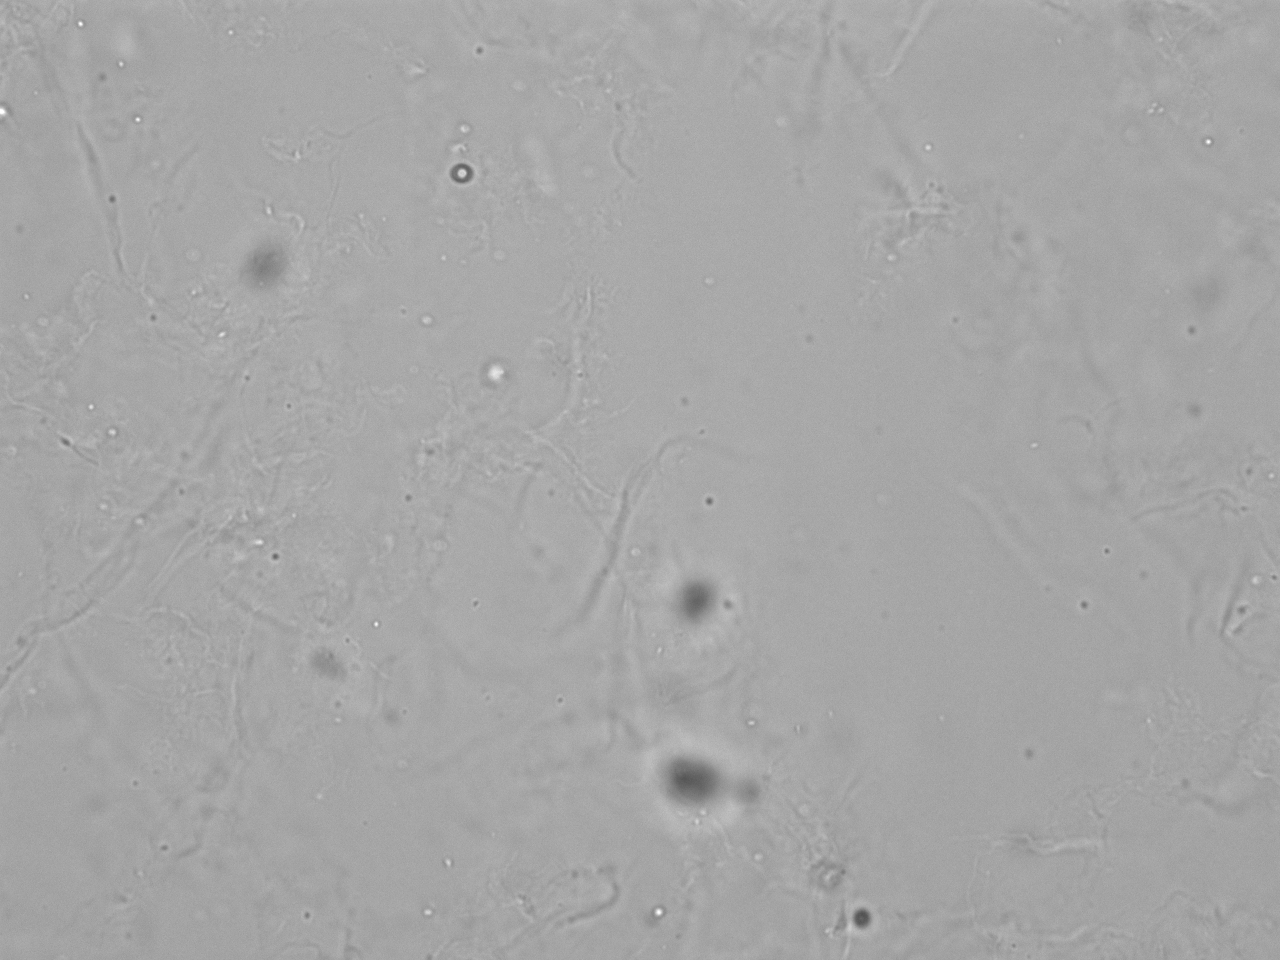

Probe mit leichter Leukozyturie und Mikrohämaturie; Bildmaterial für Explorer-Demo.

Mikroskopie-Bilder